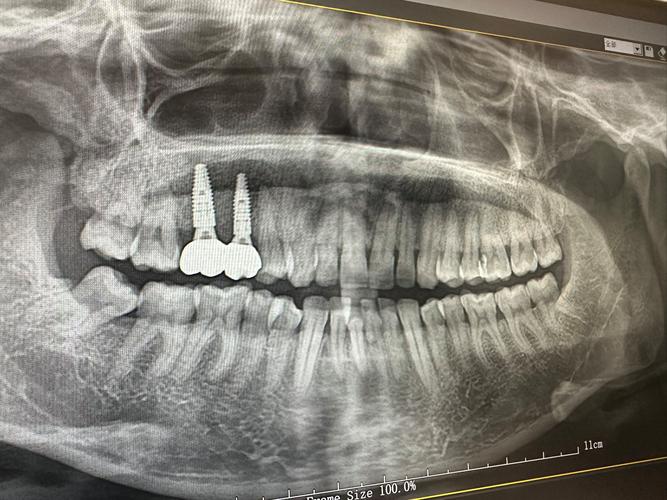

- 骨量(高度和宽度): 种植体需要植入足够的骨组织中才能稳固,X光(尤其是全景片和CBCT)能精确测量牙槽骨的高度、宽度和密度,判断是否足够容纳种植体。

- 下牙槽神经管: 在下颌后牙区,种植体必须避开下牙槽神经,否则会导致下唇、下巴麻木甚至永久性损伤,X光能清晰显示神经管的位置和走向。

- 上颌窦: 在上颌后牙区,种植体不能穿入上颌窦,X光能显示上颌窦底的位置、大小和形态,帮助医生确定种植体植入的安全深度和位置。

- 邻牙牙根: 确保种植体不会损伤邻牙的牙根。